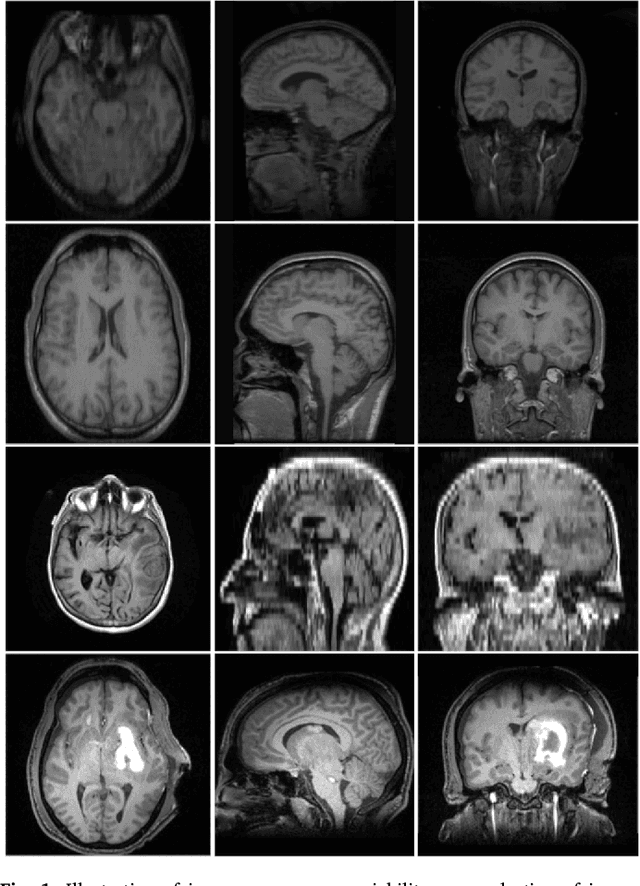

Abstract:Brain extraction from images is a common pre-processing step. Many approaches exist, but they are frequently only designed to perform brain extraction from images without strong pathologies. Extracting the brain from images with strong pathologies, for example, the presence of a tumor or of a traumatic brain injury, is challenging. In such cases, tissue appearance may deviate from normal tissue and violates algorithmic assumptions for these approaches; hence, the brain may not be correctly extracted. This paper proposes a brain extraction approach which can explicitly account for pathologies by jointly modeling normal tissue and pathologies. Specifically, our model uses a three-part image decomposition: (1) normal tissue appearance is captured by principal component analysis, (2) pathologies are captured via a total variation term, and (3) non-brain tissue is captured by a sparse term. Decomposition and image registration steps are alternated to allow statistical modeling in a fixed atlas space. As a beneficial side effect, the model allows for the identification of potential pathologies and the reconstruction of a quasi-normal image in atlas space. We demonstrate the effectiveness of our method on four datasets: the IBSR and LPBA40 datasets which show normal images, the BRATS dataset containing images with brain tumors and a dataset containing clinical TBI images. We compare the performance with other popular models: ROBEX, BEaST, MASS, BET, BSE and a recently proposed deep learning approach. Our model performs better than these competing methods on all four datasets. Specifically, our model achieves the best median (97.11) and mean (96.88) Dice scores over all datasets. The two best performing competitors, ROBEX and MASS, achieve scores of 96.23/95.62 and 96.67/94.25 respectively. Hence, our approach is an effective method for high quality brain extraction on a wide variety of images.

Abstract:Registration involving one or more images containing pathologies is challenging, as standard image similarity measures and spatial transforms cannot account for common changes due to pathologies. Low-rank/Sparse (LRS) decomposition removes pathologies prior to registration; however, LRS is memory-demanding and slow, which limits its use on larger data sets. Additionally, LRS blurs normal tissue regions, which may degrade registration performance. This paper proposes an efficient alternative to LRS: (1) normal tissue appearance is captured by principal component analysis (PCA) and (2) blurring is avoided by an integrated model for pathology removal and image reconstruction. Results on synthetic and BRATS 2015 data demonstrate its utility.